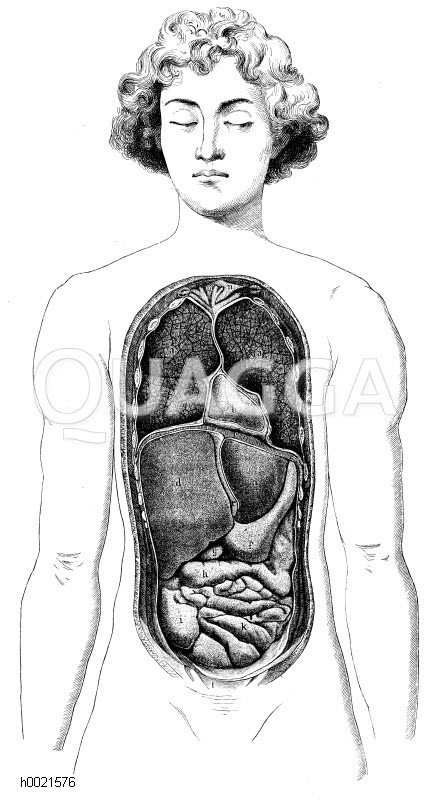

Vorderansicht der Brust- und Baucheingeweide: Zeichnung/Illustration/Holzstich – – Front view of the thoracic and abdominal viscera –

Bildnr.: h0021576

Bildtyp: Holzstich

Erscheinungsdatum: 1894

Anatomy; graphics; Woodcut; Wood engraving; Wood engravings; illustration; Illustrations; man; stitch; Line drawing; xylograph; woodcut; drawing; historically; black and white; vintage,